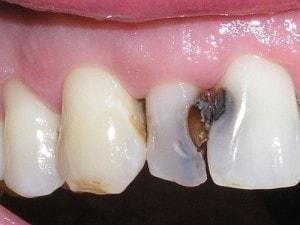

Composite buildup

Tooth #7 is vital

Crown would require root canal and post for retention. Unfortunately, there is no ferrule for a crown.

Pre-opt incisal view

PA #7